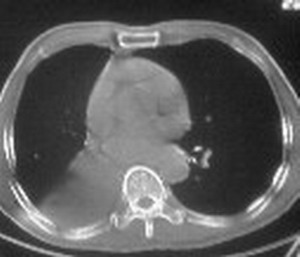

右肺下叶支气管闭塞,中间段支气管狭窄,下叶不张,胸腔及叶间积液.中心型肺癌伴下叶肺不张.胸腔和叶间积液.

右肺下野后部均匀低密度影,边缘锐利,前缘外突(不支持肺不张),纵隔内未见明显肿大淋巴结,右下肺门结构显示欠清,临床资料太过简单,考虑右侧后胸部包裹性积液。其他待排。建议密切结合临床其他检查。

ct值12,包裹性胸腔积液,